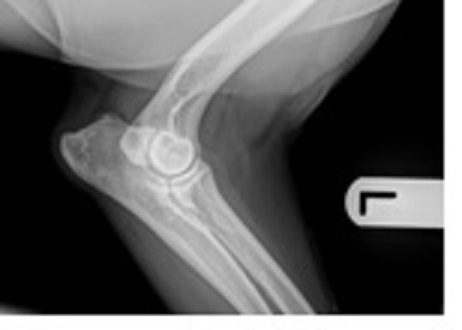

Elbow dysplasia (ED) is one of the most common causes of thoracic limb lameness in Labradors and other large- and giant-breed dogs (Michelsen, 2013). ED is a term used to describe the presence of one or more developmental conditions that involve the elbow joint.

This collective term includes conditions such as medial coronoid disease (MCD), radio-ulnar incongruity, ununited anconeal process (UAP) and osteochondrosis (OCD) (Cook and Cook, 2009; Kirberger and Fourie, 1998; Michelsen, 2013; Samoy et al., 2006). These conditions develop in juvenile animals and clinical signs (pain and lameness) are often present at four to six months of age. However, many dogs do not present until much later, when their osteoarthritis (OA) is advanced and lameness is a constant feature.

In addition to the mechanical effects of altered gait, elbows that have advanced OA changes commonly have a significant reduction in range of motion (ROM). This is due to new arthritic bone formation throughout the joint and thickening and fibrosis of the joint capsule, physically obstructing joint flexion and extension. This, in turn, has secondary consequences that result in shoulder tendon degeneration. Disease or degeneration in other parts of the body or other limbs can also play a role due to compensatory adaptations to lameness and pain.

RM is a targeted treatment that requires a holistic approach to treat all causes of pain and degeneration in the body simultaneously to get the best treatment responses. Greenside, therefore, perform a thorough physical examination and further diagnostic tests (X-rays and musculoskeletal ultrasound) to diagnose concurrent orthopaedic musculoskeletal conditions. All musculoskeletal diseases are amenable for treatment using RM if correctly diagnosed and specifically targeted – this includes many spinal conditions. Bloods are also taken to look at the patient’s general health profile and check thyroid levels, as other non-orthopaedic disease processes can affect treatment outcomes if not identified.